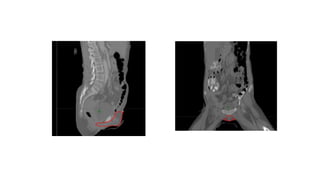

>> PRE-OPERATIVE VULVAR PRIMARY:

• CTV = GTV + 1 cm

• Including the entire vulva (+/− perineum, vagina, or urethra if

involved) with editing to exclude uninvolved bone, muscle, and

adjacent organs

• #72 Coronal images can be useful for identifying the lateral extent of the vulva (white arrow), and on the sagittal images extension into the vagina is specifically included within the CTV (red arrows).